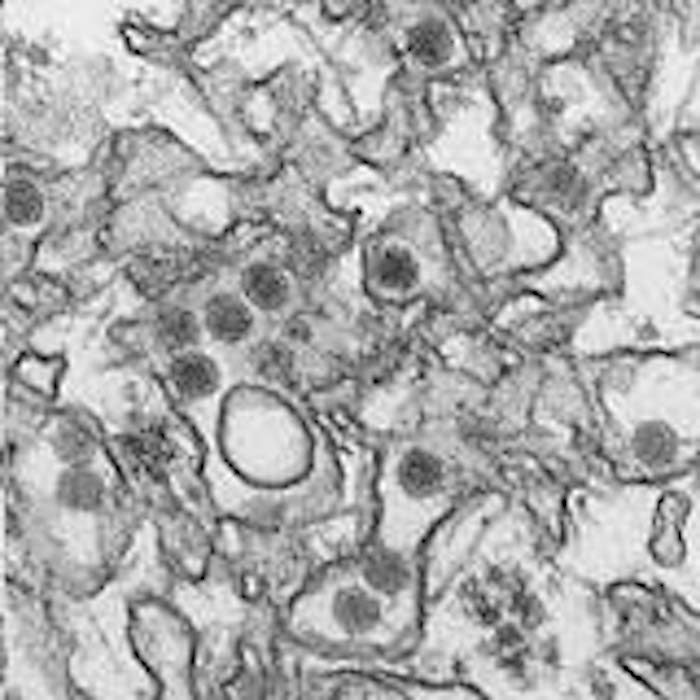

El virus zika fue descubierto por primera vez en monos en Uganda en 1947. Su nombre proviene de la selva zika donde fue descubierto. Es originario principalmente de la zona tropical de África, pero también se han detectado brotes en el sureste de Asia y las islas del Pacífico. Apareció en Brasil hace años y, desde entonces, se conocen casos en muchos países de América Latina y el Caribe.